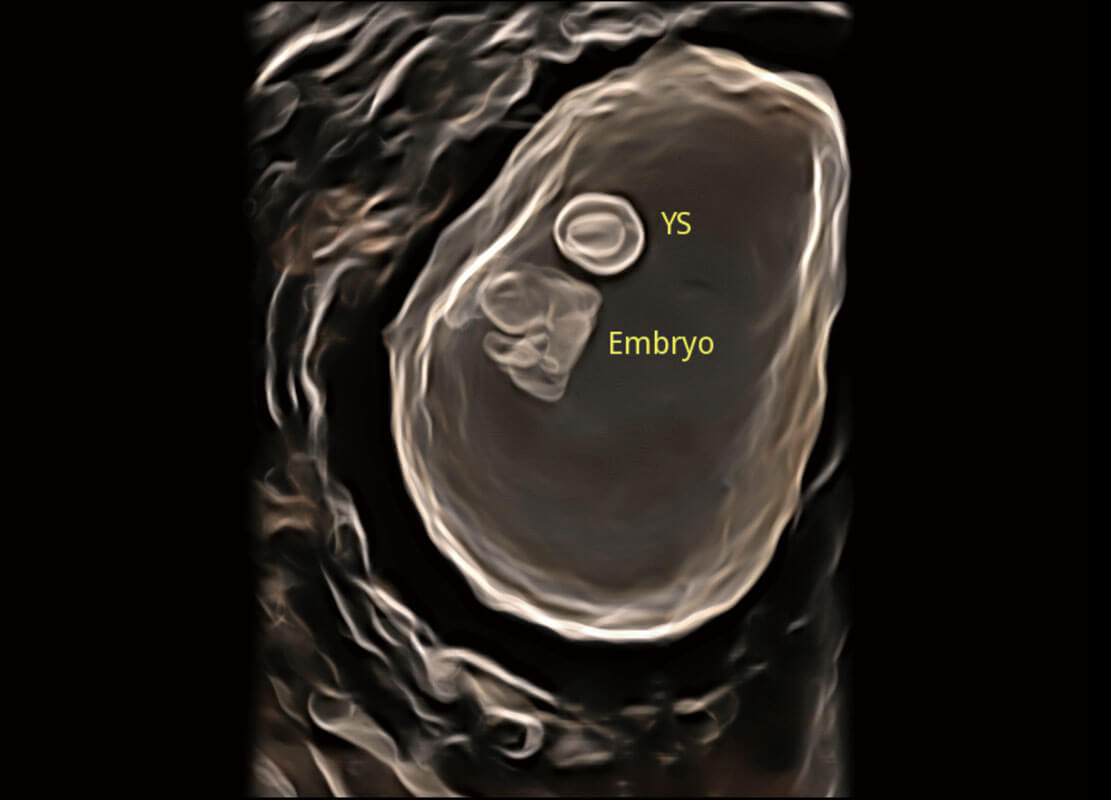

• 光影成像-孕囊